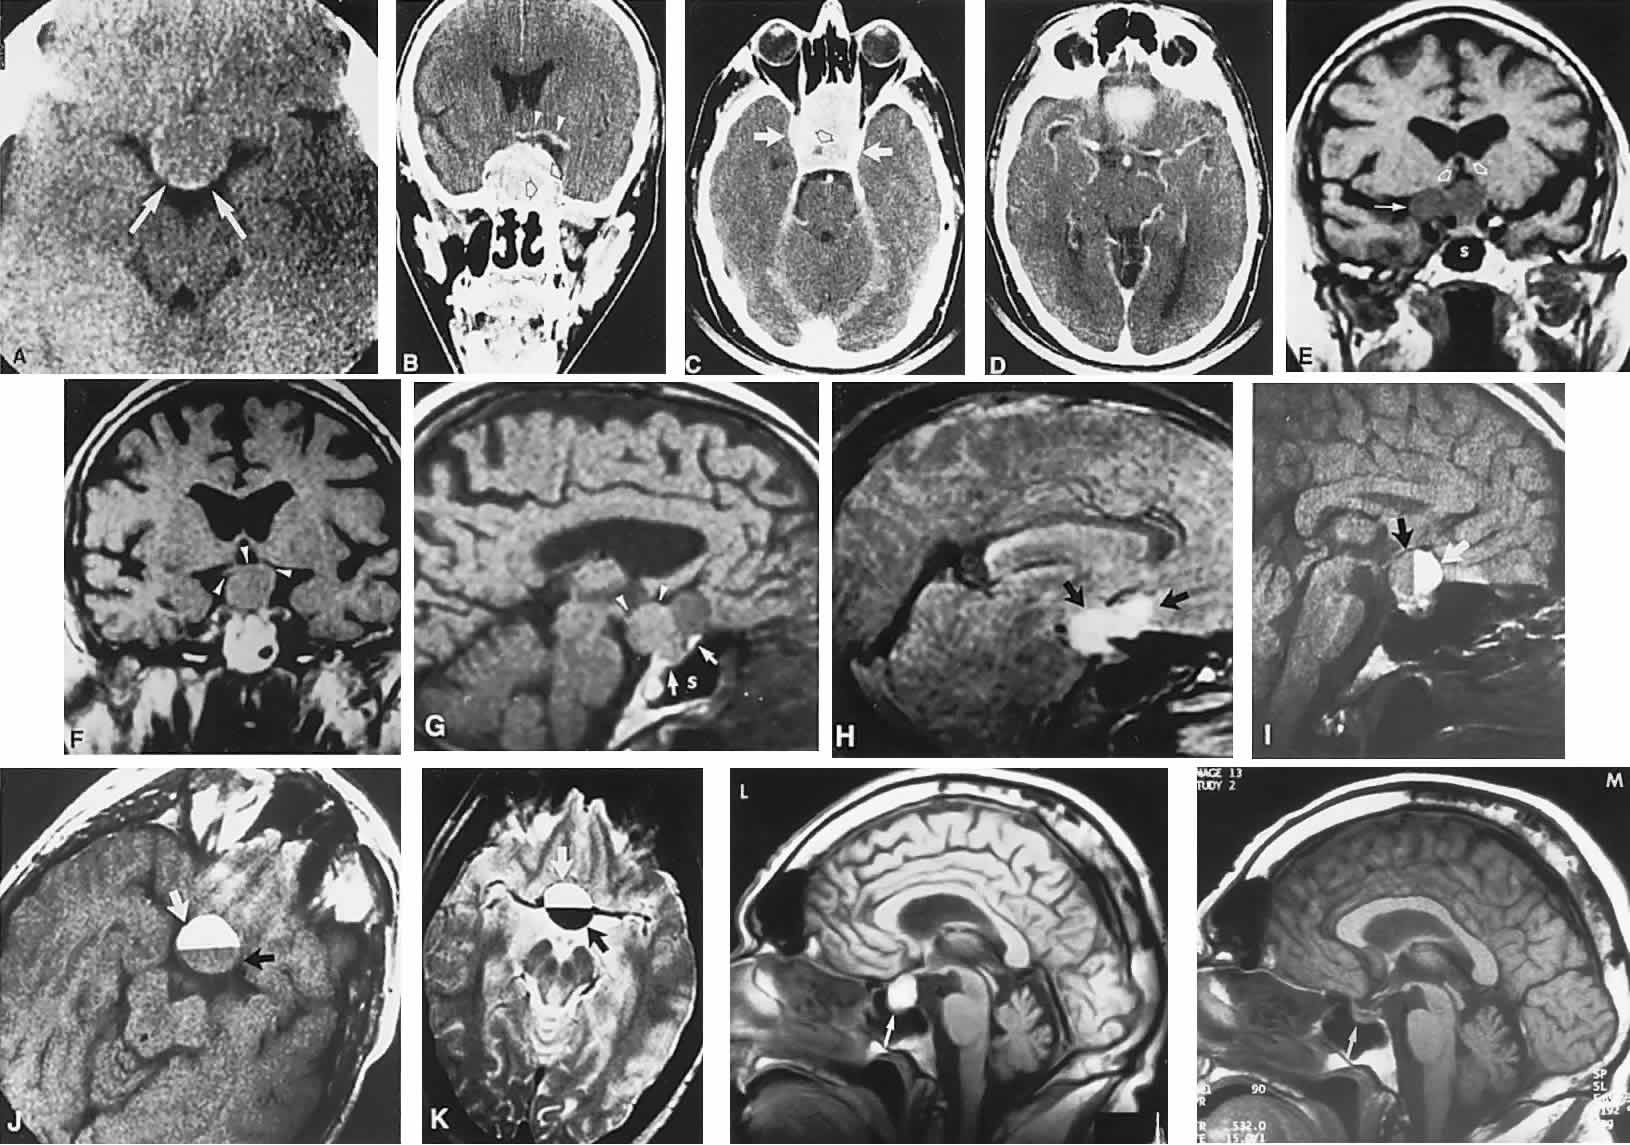

Fig. 3. Neuroimaging of pituitary adenomas. A. Axial computed tomography (CT) section shows a round tumor mass filling the suprasellar cistern; ring enhancement (arrows) indicates subcapsular hemorrhage. B. Contrast-enhanced coronal CT section through a large invasive adenoma. Note encasement of the carotid artery (arrows) and the position of the middle cerebral artery above (arrowheads). C. Axial CT section shows lateral expansion into the cavernous sinuses (white arrows) and a necrotic cyst (black arrow). D. Subfrontal superior extent of the mass. Note the middle cerebral arteries. E. Magnetic resonance imaging of a large lobulated prolactinoma, with suprasellar extension. Note the distortion of the third ventricle (open arrows) and extension toward the temporal lobe (long arrow); the tumor has not involved the sphenoidal sinus (s). F. Chiasm (arrowheads) is draped on the superior surface of the tumor (TR, 550 milliseconds; TE, 26 milliseconds). G. Sagittal section shows suprasellar growth with the chiasm above (arrowheads); the sella (arrows) and sphenoidal sinus (s) are normal (TR, 850 milliseconds; TE, 26 milliseconds). H. Hyperintense signal (TR, 2000 milliseconds; TE, 60 milliseconds) indicates the partial cystic character. Sagittal (I) and axial (J) sections with head tilt to the right, in case of a large cystic adenoma with an interface level between newer blood (white arrow) and older blood (black arrow) (TR, 800 milliseconds; TE, 30 milliseconds). K. Signal difference is intensified (TR, 2100 milliseconds; TE, 80 milliseconds). L. Hemorrhage (bright signal, arrow) in a pituitary adenoma with headache and bitemporal field depressions. M. Without interventions, 2-month follow-up showed spontaneous involution, with normal pituitary gland (arrow), stalk, and chiasm.

Imaging of Pituitary Tumors

In addition to the radiologic implications mentioned previously, specific points should be emphasized. Contrast-enhanced CT and, especially, MRI have replaced all previous radiologic techniques in the detection and anatomic assessment of sellar and juxtasellar lesions. MRI has also the inherent advantage of using no radiation, nor does it require iodinated contrast injections. Although thin-section contrasted CT does indeed disclose most lesions, bone changes, and recent hemorrhage, MRI is superior in delineating distortions of optic nerves and chiasm, in displaying arteries, and in revealing fat, hemorrhage, or cyst (see Figs. 3E through M). Indeed, in a prospective study of normal volunteers, gadolinium-enhanced MRI disclosed pituitary adenomas (3 mm to 6 mm in diameter, i.e., microadenomas) in 10% of adults aged 18 to 60 years.66 T2-weighted fast spin-echo MRIs are currently the most precise sequence for demonstrating the optic nerves and chiasm, even when these structures are severely distorted by suprasellar tumor extension.67